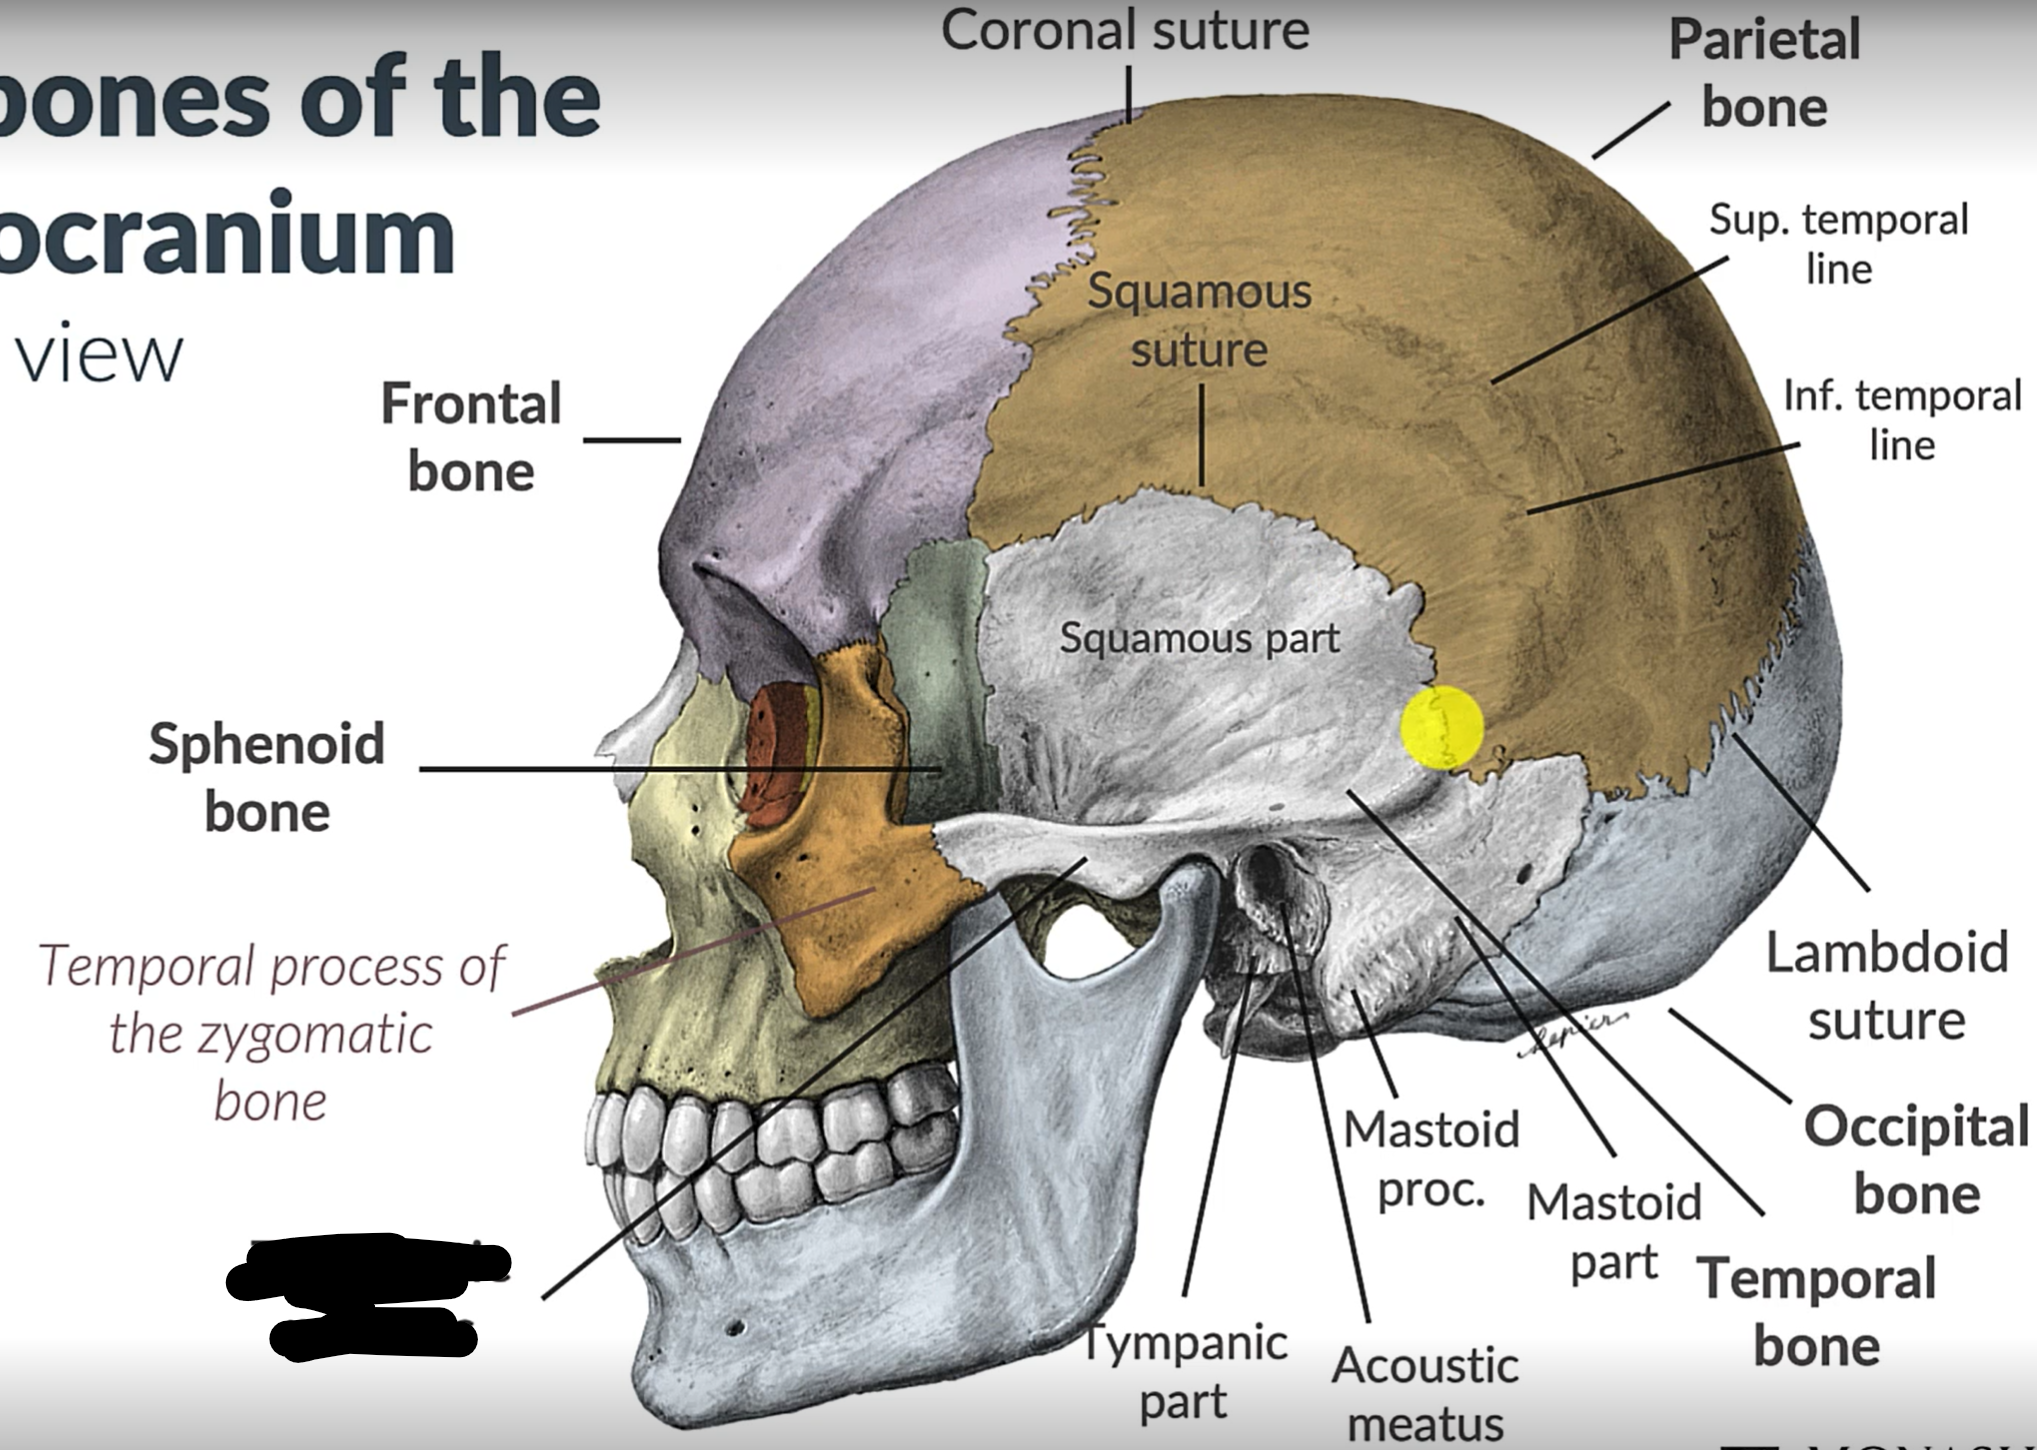

Parietal bone

Frontal bone

Temporal bone

Sphenoid bone

Zygomatic bone

Coronal suture

Squamous suture

Lambdoid suture

Occipital bone

Temporal bone

Zygomatic process

Sphenoid bone